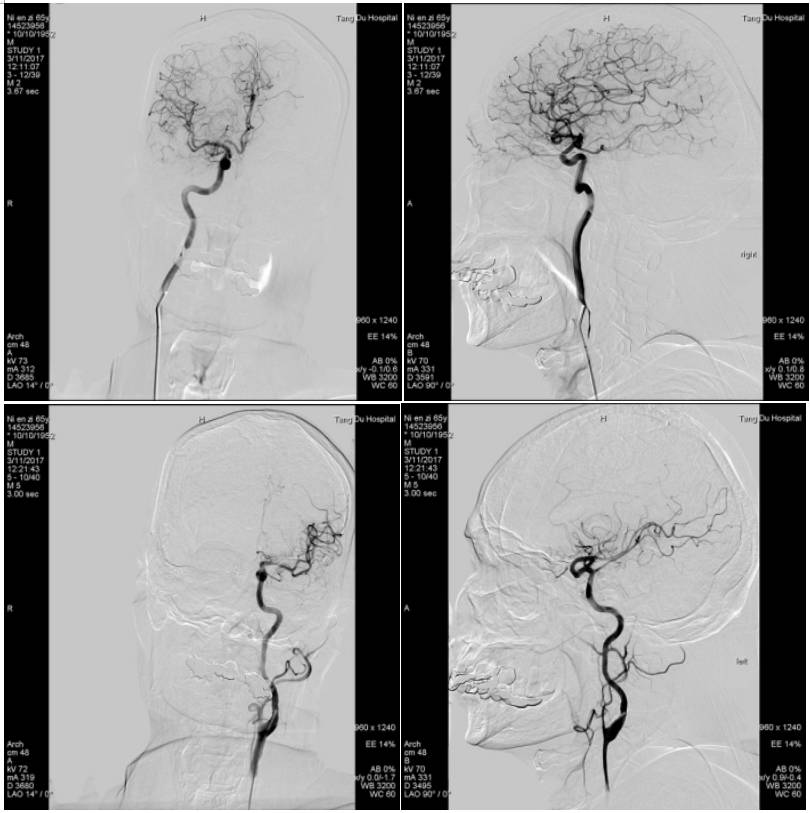

完善相关检查后,急诊行全脑血管造影术

示右侧大脑后动脉P1段不显影,右侧后交通动脉开放。左侧P1中段闭塞,左侧前循环无明显代偿。考虑该血管为责任血管,急诊行血管开通术。

术中用微导管将支架放置狭窄部位,术中见支架Mark显影良好,释放支架5分钟,回收支架,可见支架上附着血栓。

行血管造影示:双侧大脑后动脉显影,远端血管快速充盈,TICI:3级,术毕。患者言语较前流利,可准确应答,左侧肌力恢复正常,NHISS评分1分。